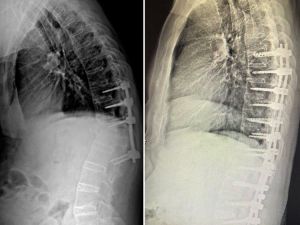

Hem kamburluğu giderildi hem de sağlığına kavuştu

2020 Skolyoz hastası Sude’ye şifa getirdi